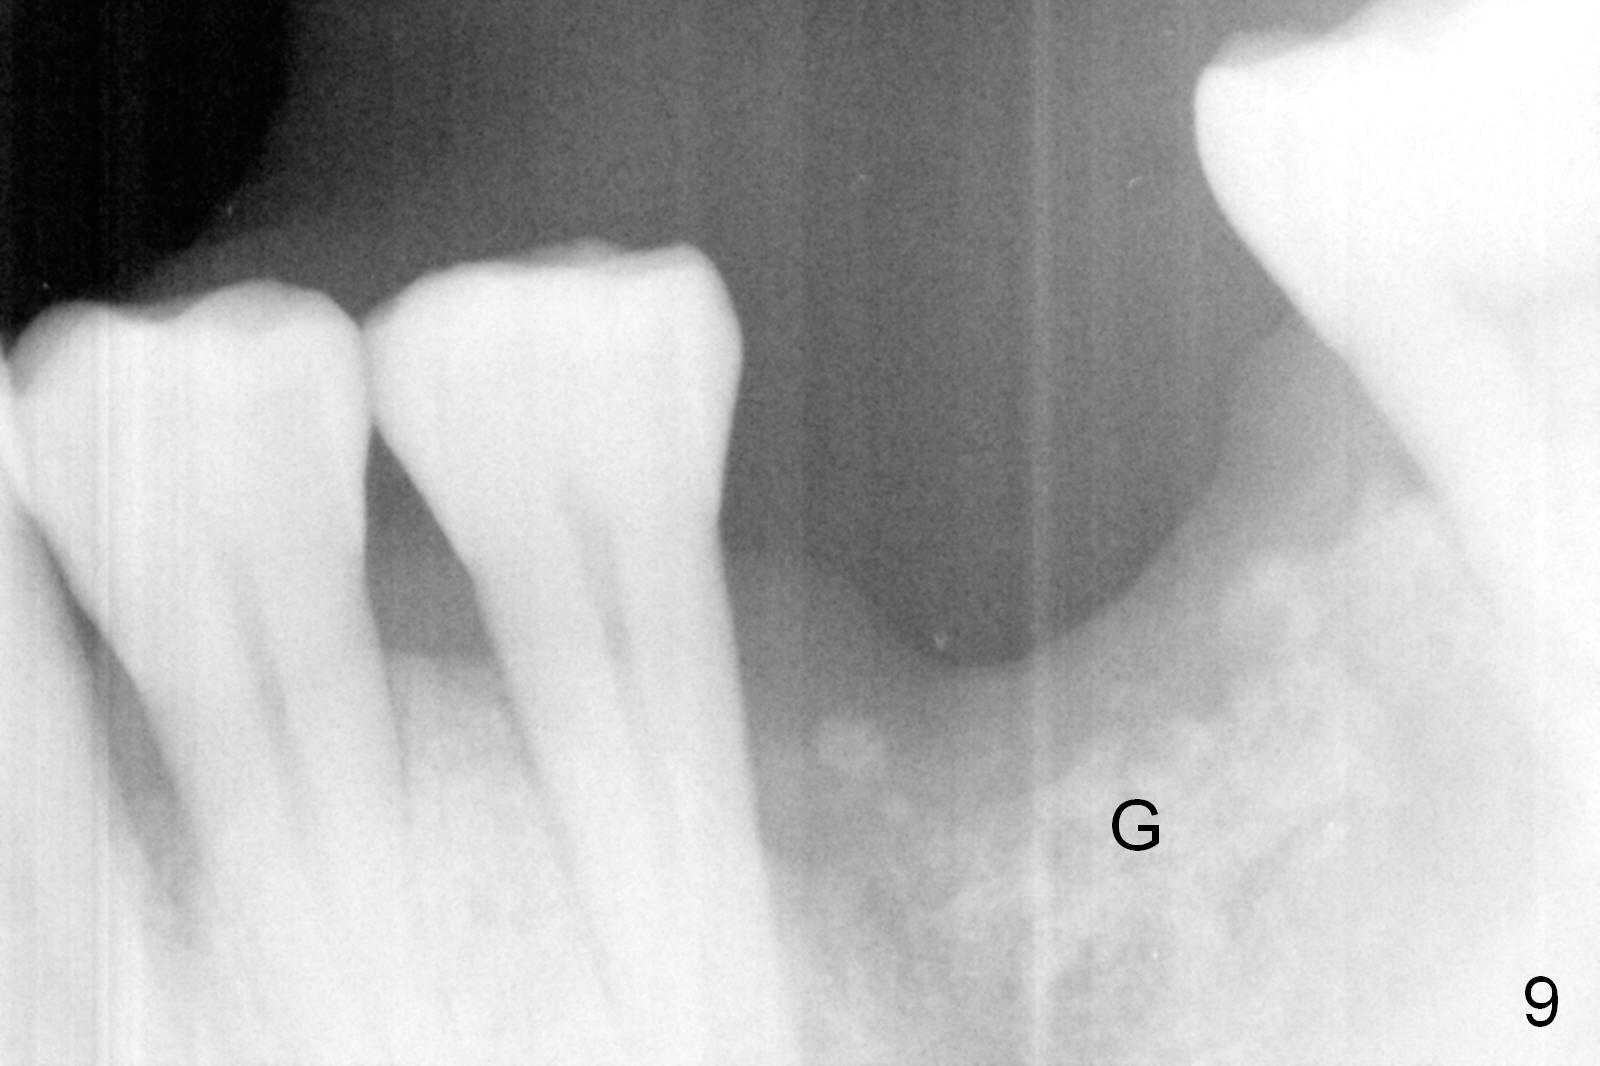

When he returns from abroad 6 weeks postop, the implant is found to be loose most likely due to retention of a piece of gauze in the mesial socket for hemostasis.  The distal socket is also low.  After debridement, socket preservation is accomplished with allograft and Osteogen, covered with Collagen plug (Fig.9).  Early removal of the retained gauze may save the implant.  The tooth #3 also has severe periodontitis.  What is new strategy?